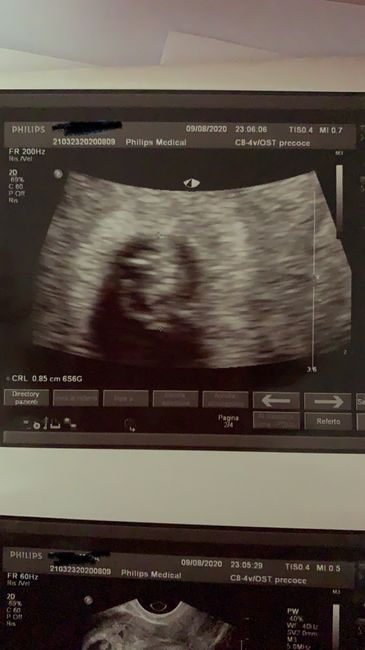

Salve ragazze , così per curiosità e per gioco vorrei sapere che se sarà un maschietto o una femminuccia . Da premettere che stranamente non ho preferenze e la certezza del sesso non l’avrò io ma l’organizzatrice del mio matrimonio che farà una sorpresa a tutti noi . Questa è la mia eco fatta ieri a 7+4 interna Esperte Metodo Ramzi 1